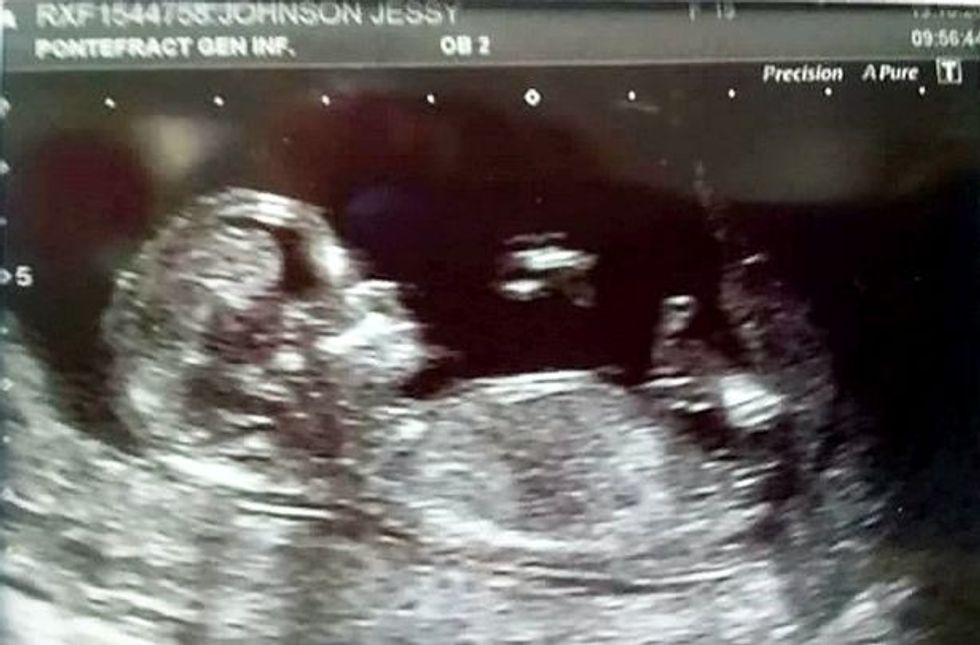

Vetëm pesë ditë para se të sillte në jetë foshnjën, Jessy Johson 19-vjeçe, u rrëzua pa vetëdije në tokë nga dhimbjet e mëdha që i kishte në bark, kur i dashur i saj që ishte nën ndikim të alkoolit e godit me shkelm, transmeton Telegrafi.